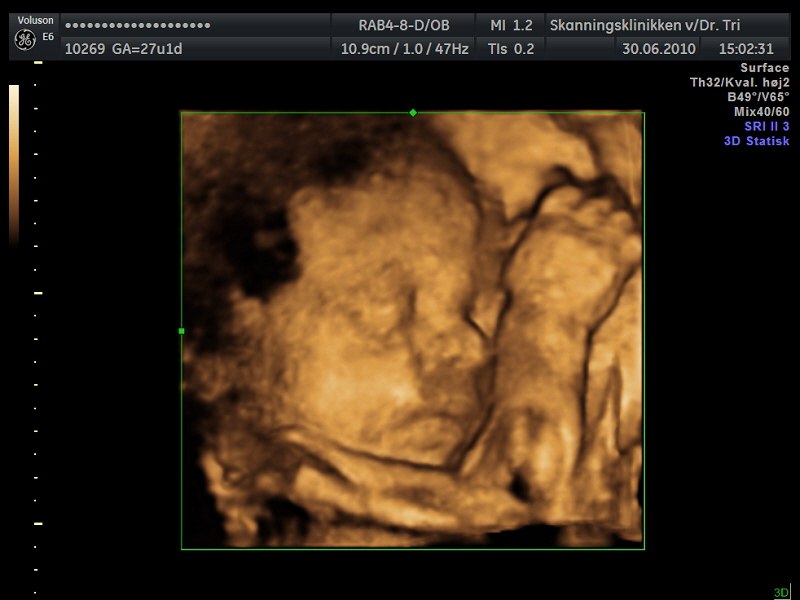

billede 3 : kønsscanning